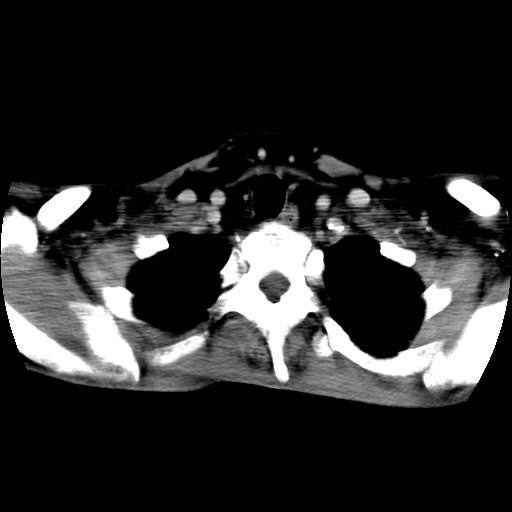

标题: CT24019:男,45岁,发现颈部肿物5个月。 [打印本页]

男,45岁,发现颈部肿物5个月,彩超示:双侧颈部及下颌部软组织增厚。

考虑双侧颈项部良性对称性脂肪增多症。